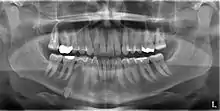

Mandibular canine impacted in the chin

3D CT of mandibular canine impacted in the chin